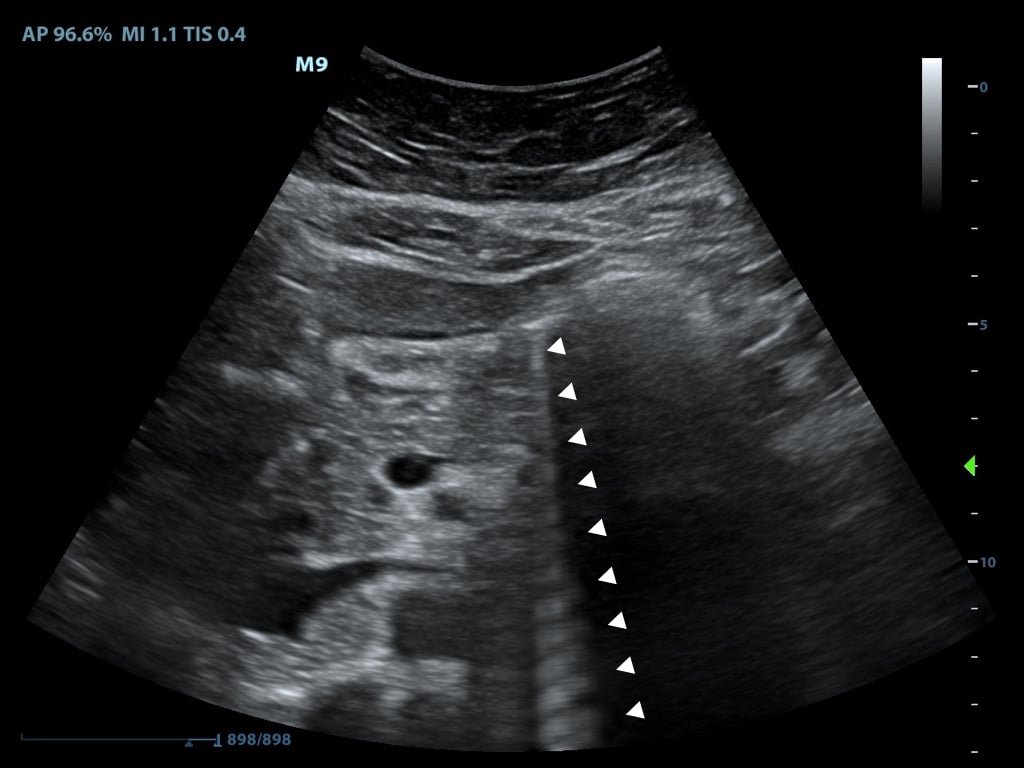

- In posterior enhancement, the area behind an echo-weak or echo-free structure appears brighter (more echogenic) than its surrounding structures

- Neighboring signals must pass through more attenuating structures and return with comparatively weaker echoes

- A common place for this to occur is posterior to the anechoic bladder (Figure 8)

- Figure 8. Posterior acoustic enhancement deep to the bladder and side lobe artifact